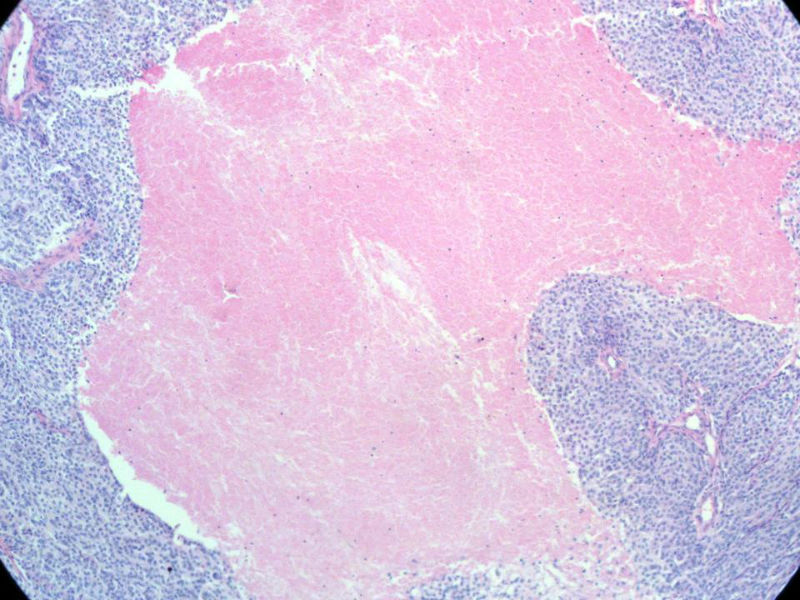

请教:本例患者曾做过介入肿瘤栓塞,图片内的坏死改变应该归为栓塞性梗死,还是肿瘤性坏死?两者形态上有区别吗?

梭形细胞与上皮样漩涡状结构,富于细胞,见个别沙砾体,并见肿瘤性坏死。颅骨及其横纹肌等软组织内见肿瘤呈侵袭性生长。但细胞异型性不是很大。鉴别:

1)恶性脑膜瘤

2)非典型性脑膜瘤

由于非典型性脑膜瘤也可以发生地图状坏死,甚至侵袭性生长。需要计数核分裂数/10HPF,以资鉴别诊断。